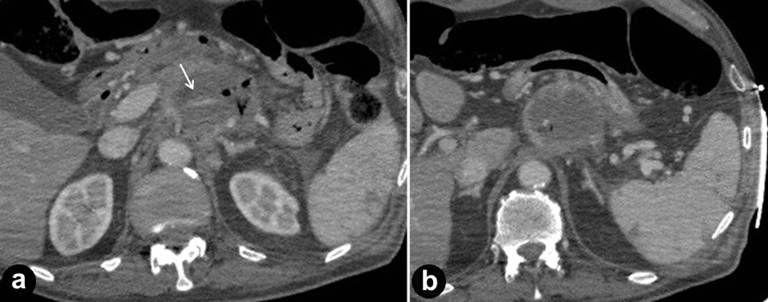

During the procedure no arrhythmias were registered. Percutaneous ablation was performed in two sessions. Five 15 cm monopolar probes (Nanoknife®, AngioDynamics, Latham, New York, NY, USA) were placed within the tumor under US guidance in a pentagon configuration, with a distance of 1.8 cm from each other. CT imaging without contrast medium was performed to evaluate needle positioning and check correct inter-probe distance (Figure 1). All probes had 1 cm of electrode exposure. Six pairs of needles were chosen with maximum and minimum inter-probe distance of 2.9 and 1.3 cm, respectively. All pulses were administered in the absolute refractory period with use of electrocardiographic synchronization to avoid triggering ventricular arrhythmia. IRE was delivered by 90 pulses for each pair of needles. A test-cycle of ten pulses was delivered to verify the correct settings of parameters (Volts, pulse length, probes’ distances) and to assess the baseline current absorbed (Amperes). Three pairs of needles (2-5, 4-1, 5-1) showed high values of Amps after test cycle so the Volt/cm was reduced of 10% to avoid reaching the limit of 50 Amps, the limit for thermal-like necrosis. After the delivery of residual 80 pulses for each pair of needles, the current absorbed showed a correct increase in value as a result of increased local permeability due to massive cytoplasm emission from destroyed cells’ membrane. An overlapping ablation was performed after pullback needles of 1cm with use of a similar protocol and similar results.

Figure 1. CT imaging without contrast medium was performed to evaluate needle positioning and check correct inter-probe distance. |